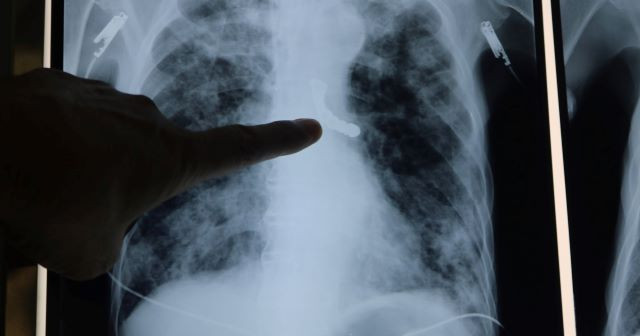

Ngày 13/8, trong quá trình nằm viện để điều trị di chứng do tiền sử lao phổi cách đây 6 năm, trong một cơn ho khạc đờm mạnh, toàn bộ hàm răng giả của cụ bị rơi và mắc kẹt vào khí phế quản gốc bên trái. Sự cố này đã gây tắc nghẽn đường thở và đe dọa tới tính mạng người bệnh.

| Phim chụp dị vật trong phế quản (BVCC). |

Trước đó năm 2018, Bệnh viện cũng tiếp nhận một cụ ông bị rơi một hàm gồm 4 chiếc răng vào phế quản. Năm nay, trường hợp cụ N.T lại bị tới 9 chiếc răng sứ kim loại với chiều dài lên tới gần 5 cm, nên quá trình nội soi lấy dị vật phức tạp hơn, đòi hỏi các chuyên gia nội soi nhiều kinh nghiệm.

Bác sỹ Nguyễn Lê Nhật Minh, Trưởng Khoa Nội soi Chẩn đoán và can thiệp cho biết: “Đây là một trường hợp dị vật khó, do bề mặt răng sứ rất trơn nên không thể dùng kìm để gắp được, hơn nữa, người bệnh còn bị suy hô hấp và đang phải thở máy.